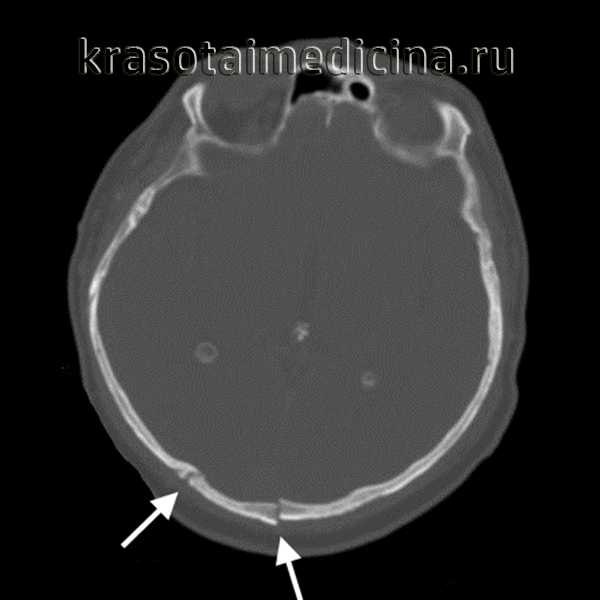

- КТ черепа. Обычно проводится при подозрении на линейный перелом и сомнительных результатах рентгенографии. На послойных снимках обнаруживается положительный «симптом молнии» (линия, идущая от наружной к внутренней поверхности кости). Иногда методика применяется для уточнения тяжести повреждения при других типах переломов.